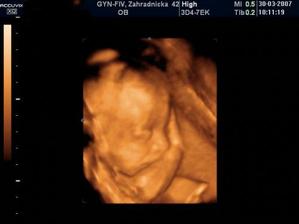

Nathan Nicolas ! bruško, pôrod a prvé mesiace

Nathan Nicolas, narodil sa v Bojnickej pôrodnici, v piatok 13. júla ráno 8:08... Mal 3020 g, 50 cm a spolu so svojim starším bratom je to najväčšie šťastie 🙂